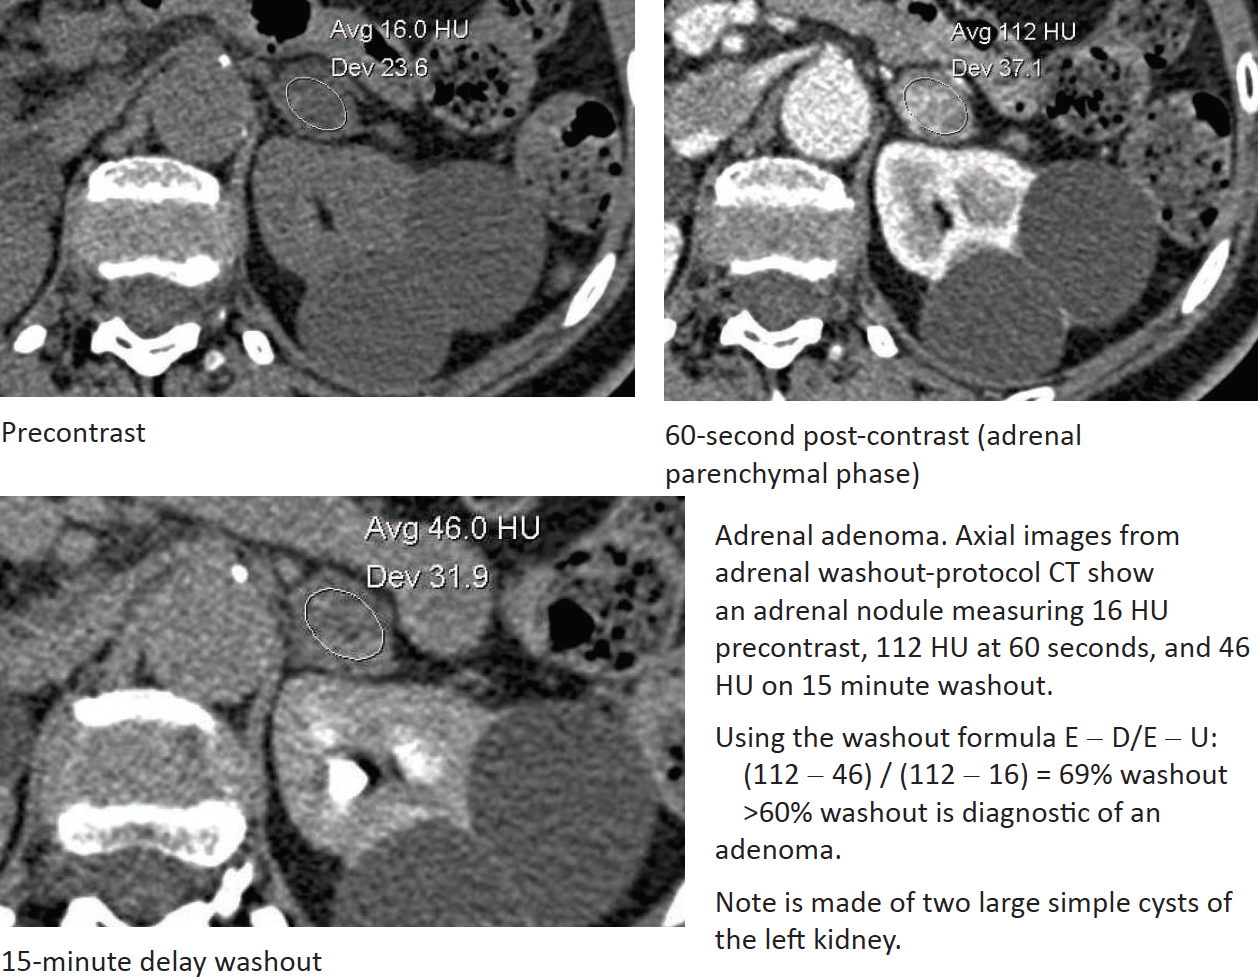

Adrenal CT Imaging

Which demonstrate more rapid contrast washout - adenomas or mets?

Timing of the washout phase?

% Washout calculation? What is diagnostic of adrenal adenoma?

What can you do if unenhanced CT is not available or not performed due to radiation exposure concern?